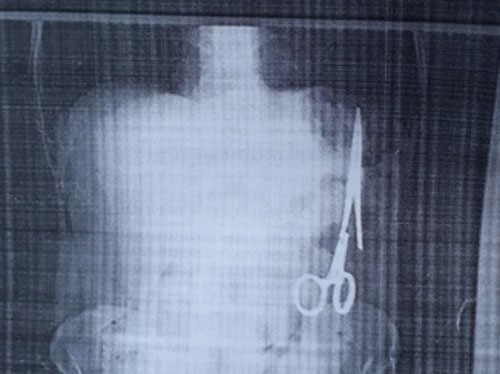

Chiếc kéo nằm trong bụng ông Nhật từ năm 1998. (TTXVN)

Kéo được lấy ra ngoài hôm thứ Bảy vừa qua. (TTXVN)

Ca mổ cho bệnh nhân Ma Văn Nhật bắt đầu lúc 12 giờ 30 trưa và kết thúc sau gần 3 tiếng đồng hồ. Chiếc kéo (panh phẫu thuật) nằm ở bên trái ổ bụng, sát đại tràng, dài 15 cm đã được lấy ra khỏi bụng bệnh nhân.

Kết quả siêu âm ngày Giáng Sinh 25 tháng 12 cho thấy trong ổ bụng của ông có một chiếc kéo dài khoảng 15 cm, được cho là chiếc panh chuyên dùng để mổ của ngành y. Hai ngày sau, ông đến siêu âm tại BV Bắc Kạn và họ cũng thấy kết quả tương tự.